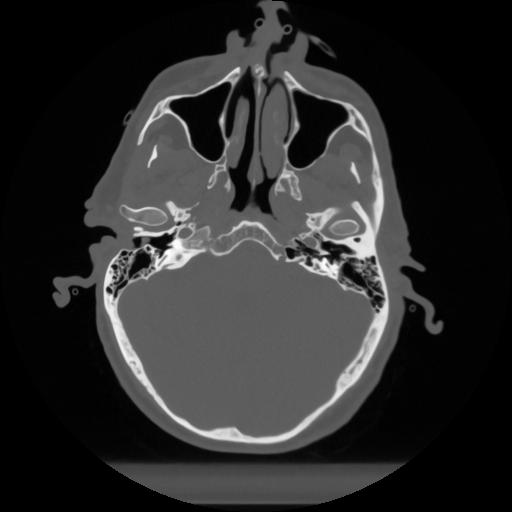

12 P.BLANDAS,,Vol,0.5,P.BLANDAS,,